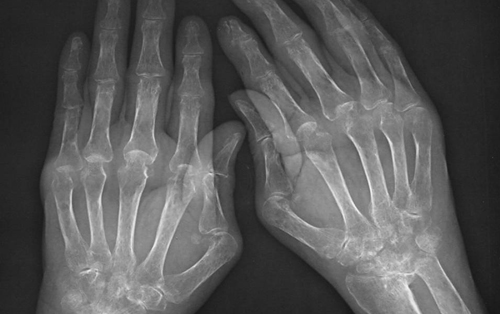

类风湿性关节炎是严重的常见自身免疫性疾病,我国总患病人数估计超过500万,如果不治疗,致残率将达70%。目前,国际上对此病广泛采用甲氨蝶呤治疗。雷公藤长期以来被中医用于治疗关节疼痛和炎症,具有较强的免疫抑制和抗炎作用。中国风湿病学之父、北京协和医院张乃峥教授早在数十年前就积极倡导推广雷公藤制剂治疗类风湿性关节炎,临床验证具有良好的疗效和成本效益比。但由于缺乏安全性和有效性的系统数据,其治疗价值未能得到国内外学术界的重视。

2012年年初,张奉春教授和张烜教授自筹经费,联合国内9家风湿病研究中心开展雷公藤多甙和甲氨蝶呤对比治疗活动性类风湿关节炎的临床研究,对207名活动性类风湿关节炎患者按照国际通行标准,进行了严格的前瞻性、随机、对照临床研究。结果显示,经过24周的治疗,单用雷公藤组取得55.1%的治疗有效率,高于单用甲氨蝶呤组的46.4%,而甲氨蝶呤与雷公藤联合用药取得高达76.8%的治疗有效率,且不同药物组间的不良反应发生率无显著性差异。